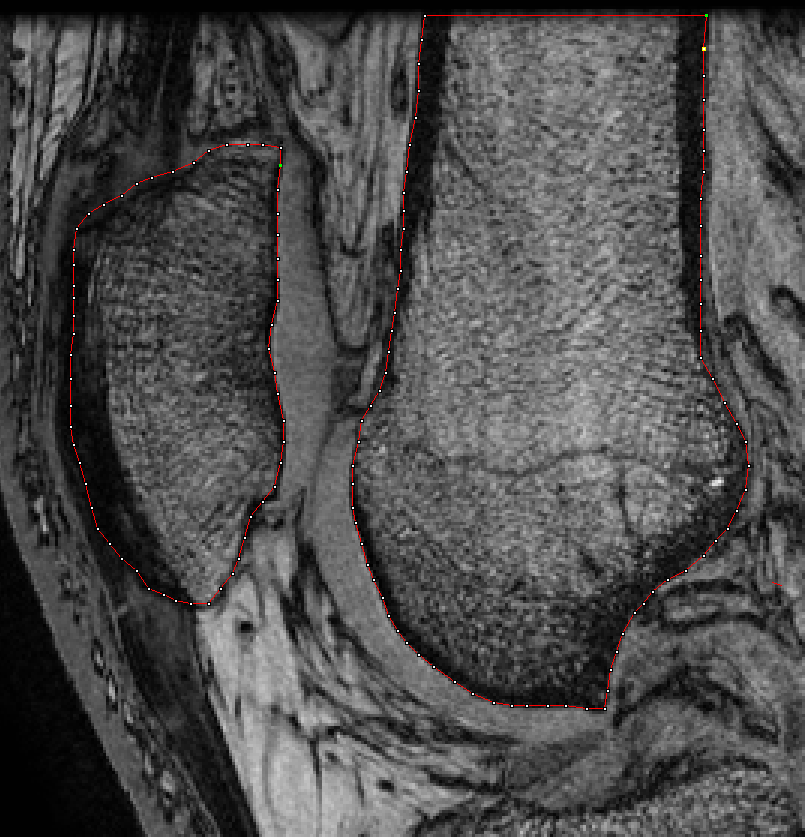

CREDO: CRiteria for the Early Diagnosis of Osteoarthritis

Developing and validating diagnostic criteria for early hip and knee osteoarthritis.